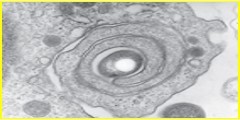

Look how pretty: